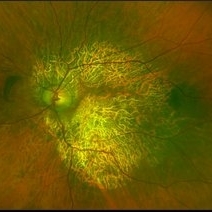

Not All Stars Are in the Sky — Some Live in the Eyes of Those Learning to See in New Ways

Not All Stars Are in the Sky — Some Live in the Eyes of Those Learning to See in New Ways

Apr 21 2025 by rohan jain

Stargardt disease

Photographer: Dr. ROHAN JAIN

Condition/keywords: fleck retinopathy, fundus autofluorescence (FAF), hereditary macular dystrophy